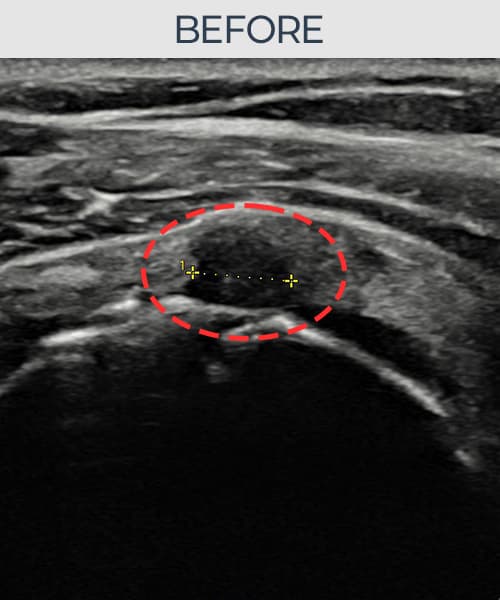

超声确认旋转肌腱袖 部分撕裂(6mm × 3mm (肌腱厚度约35%缺损))。缩小缝合术后肌腱连续性恢复,患者回归正常生活。

术前

术前超声确认旋转肌腱袖 部分撕裂,冈上肌腱回声不连续伴肌腱缺损(6mm × 3mm (肌腱厚度约35%缺损))。术后超声显示撕裂部位充满再生组织,肌腱连续性恢复,回声模式正常化。

该患者持续肩痛。详细超声检查确认旋转肌腱袖 部分撕裂(缺损:6mm × 3mm (肌腱厚度约35%缺损))。在超声引导下实施非手术缩小缝合术。术后佩戴支具约4-6周,随后进行分阶段康复锻炼。随访超声确认肌腱连续性恢复、结构稳定,患者顺利回归日常生活。